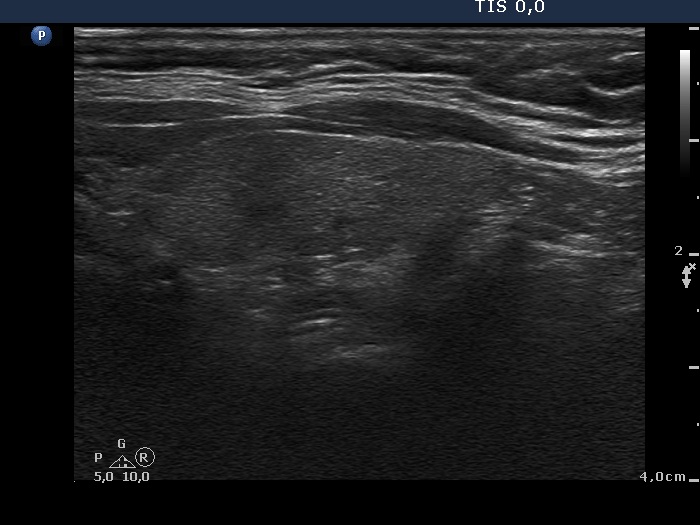

Parathyroid lesions - case 976 (ultrasonographic picture 6)

Right lobe, longitudinal scan